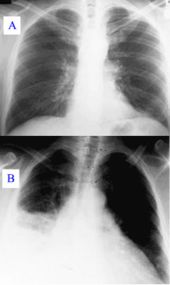

An important test for pneumonia in unclear situations is a chest x-ray. Chest x-rays can reveal areas of opacity (seen as white) which represent consolidation. Pneumonia is not always seen on x-rays, either because the disease is only in its initial stages, or because it involves a part of the lung not easily seen by x-ray. In some cases, chest CT ( computed tomography) can reveal pneumonia that is not seen on chest x-ray. X-rays can be misleading, because other problems, like lung scarring and congestive heart failure, can mimic pneumonia on x-ray. Chest x-rays are also used to evaluate for complications of pneumonia ( see below.)